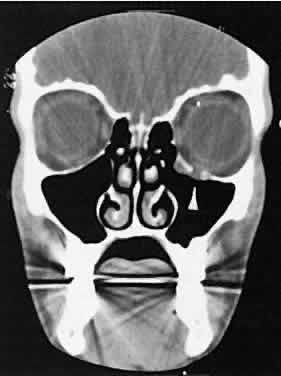

| In a qualitative way, CT scanning has redefined some of the concepts regarding

nonspecific orbital inflammations (orbital pseudotumor). We now

appreciate that any or all structures within the orbit or orbits may

be affected. Inflammation can be localized to an EOM (myositis), lacrimal

gland (dacryoadenitis), optic nerve sheath (perioptic neuritis), orbital

soft tissues (nonspecific inflammation), posterior scleritis, or

trochlea (trochleitis). There is no satisfactory explanation about

why or how this inflammation occurs and remains so localized, although

some types may be associated with various systemic diseases such as sarcoidosis, Wegener's

granulomatosis, or other vasculitic conditions. The CT characteristics of each subgroup are different and are considered separately. The nonspecific inflammation, if diffuse and acute, can affect the entire orbit with an amorphous infiltrate, which enhances with contrast (Fig. 4).13,14 The inflammation has been reported on occasion to spill over into the nasal15–18 and intracranial compartments.19–29 Chronic inflammation also may appear dense and relatively homogeneous. The margins may or may not be regular, and the lesions usually enhance with contrast. Changes in the adjacent bone, either sclerosis or hyperostosis or both, were seen on the CT in 30 (17%) of 176 patients with biopsy-proven pseudotumor.30

The CT evaluation of orbital myositis may show diffuse irregular enlargement of one or more EOMs; enlargement can be bilateral (Fig. 5). Incontradistinction to Graves' orbitopathy, involvement of the tendinous insertion and edema ofthe adjacent fat may be noted. Other conditions associated with EOM enlargement are listed in Table 2.31–33

Nonspecific inflammatory dacryoadenitis shows enlargement of the lacrimal gland, which typically molds to the shape of the globe (Fig. 6). The adjacent bone is normal, and contrast enhancement of the gland usually is fairly homogeneous. Bilateral involvement may be apparent with certain conditions such as Sjogren's syndrome, sarcoidosis, lymphoma, or even Graves' orbitopathy, although enlarged EOM in the latter condition might make this a more obvious diagnosis.